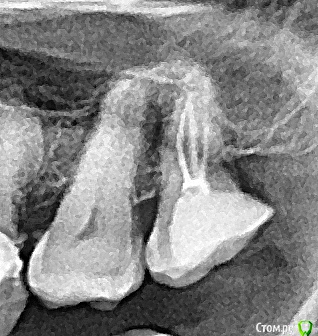

Romanson Опубликовано 9 февраля, 2019 Поделиться Опубликовано 9 февраля, 2019 Всем приветВерхний восьмой, который успел сместиться на место 7.Жутко утомляют такие зубы1. Убрал кариес2. Коагулировал десну3. Накинул платок4. Протравил границу5. Нанес адгезив6. Восстановил стенку жидким Каков Ваш протокол в таких зубах?Как избежать подтекания в таком случае?Какой материал можно использовать для стенки, чтобы подтекание было не критично? 3 Ссылка на комментарий

Turalyon Опубликовано 4 ноября, 2019 Поделиться Опубликовано 4 ноября, 2019 Всем приветВерхний восьмой, который успел сместиться на место 7.Жутко утомляют такие зубы1. Убрал кариес2. Коагулировал десну3. Накинул платок4. Протравил границу5. Нанес адгезив6. Восстановил стенку жидким 1.jpg2.jpg3.jpg Каков Ваш протокол в таких зубах?Как избежать подтекания в таком случае?Какой материал можно использовать для стенки, чтобы подтекание было не критично? Я в подобных случаях от десны поднимаю витремером, если зуб в окклюзии то поверх композитом. 1 Ссылка на комментарий